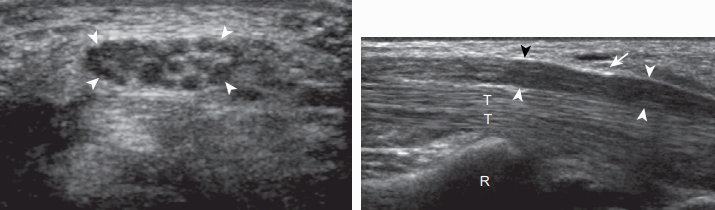

손목굴증후군(carpal tunnel syndrome) 손목굴증후군(carpal tunnel syndrome)은 팔의 죄임신경병증(entrapment neuropathy) 중 가장 흔하며, 손목부위의 정중신경에 발생한다. 정중신경은 손목굴을 지나기 때문에 외상, 덩어리, 또는 힘줄윤활막염 등에 의해 손목굴의 크기가 감소하거나 손목굴 내 구조물의 부피가 증가하면 정중신경이 압박된다. 손목굴증후군은 여자에서 더 흔하며, 손목을 과다하게 굽히면 증상이 유발된다. 초음파검사에서 정중신경은 손목굴 내로 들어가면서 에코가 낮아지고, 부기(swelling) 소견이 특징적으로 보인다. 손목주름 부위에서 정중신경의 단면적이 10㎟ 이상이면 손목굴증후군을 시사한다. 좀 더 아래쪽의 가로영상에서 지지띠가 활모양으로 휘어진 소견을 볼 수 있으며, 긴축영상에서 정중신경이 편평하게 눌린 소견을 볼 수 있다. 손가락을 움직이면서 손목굴을 검사하면 정중신경의 움직임이 감소된 소견을 볼 수 있다. 색도플러영상에서 신경내에 혈류가 보이면 손목굴증후군을 시사하는 소견으로 알려져 있다. 갈림(bifid) 정중신경 또는 정중신경이 보다 몸 쪽에서 갈라지는 경우는 정중동맥이 두 개의 신경줄기 사이에 남아있을 수 있으며 정상 인구의 2.8%에서 보이는 정상변이이다. 이로 인해 손목굴증후군이 생길 수 있으며 낮은 에코의 두꺼워진 두 개의 신경줄기의 단면적 합이 10㎟ 이상이 된다. 드물게 덩어리 또는 결절종등에 의해 정중신경이 압박될 수 있다.